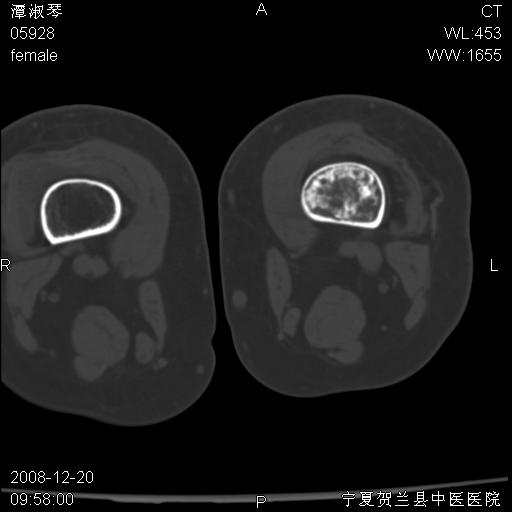

标题: CT17526:请各位看看是啥?

支持骨梗死,退行性骨关节病,膝关节积液.

考虑骨梗死可能性大

骨梗死可能性大

左股骨下段骨梗死。双膝退变。

左胫骨下端松质骨及髓腔内可见点片状高密度灶,骨皮质无明显膨胀及变薄。病变范围较长。支持骨梗死,退行性骨关节病,膝关节积液